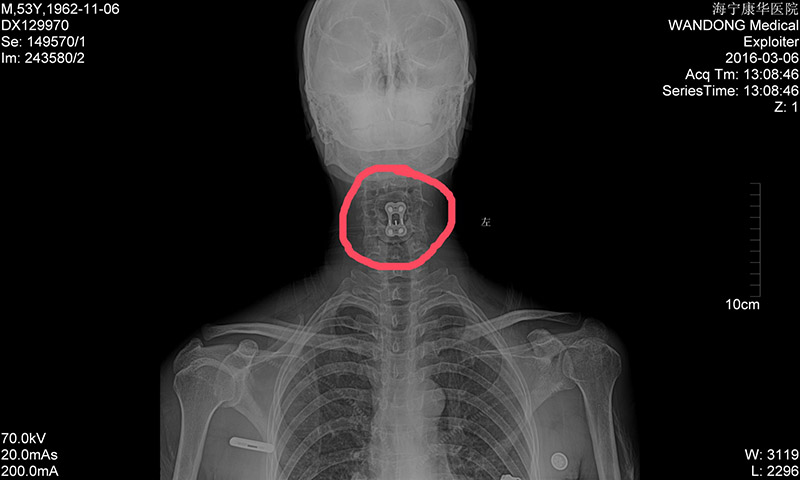

经初步诊断,老田脊髓损伤(颈段):颈椎脱位、左侧颈4椎体骨折、颈4椎板骨折、颈4棘突——高位截瘫!如霹雳般的消息传至家人耳中,妻子惊惶无措、泪流不止:才50多的人,就这样瘫了,以后家该怎么办?

8月18日,老田被第一次推进手术室进行颅骨牵引术,家人揪着心等完了全程,终于等到老田顺利出来。8月31日,老田再一次被推向手术台,妻子一直紧攥着手里的包不曾松开。门外的人坐立不安,门内——颈椎前路切开复位、钢板内固定术、颈4/5椎间融合器植骨融合术、左胫骨取骨术,一项项复杂的工作在蒋林海与张凤军的手下进行着……“成功了,没事了。”当蒋林海微笑着走出手术室,凤娟忍不住掩面而泣,连感激都梗在喉间,一个字都说不出来。